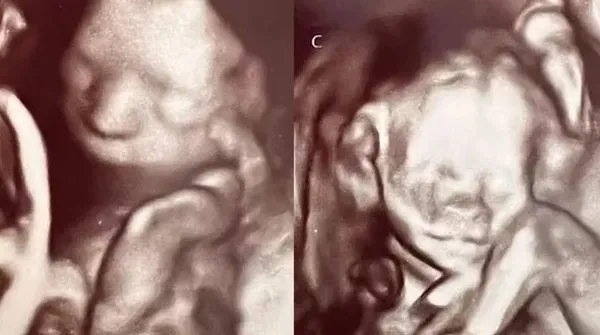

Ashley, 2 hafta sonra 47 yaşındaki erkek arkadaşı Val ile beraber ultrason kontrolüne gittiğinde sevinci büyük şoka dönüştü ve bir değil tam dört bebeğe hamile olduğunu öğrendi.

Daha önceki ilişkisinden de bir kızı olan Anne Adayı karnındaki dört bebeğin dördüz değil iki ayrı tek yumurta ikizi olduğunu öğrendi.

ABC News'de yer alan habere göre aynı anda çift ikiz bebeğe sahip olmak nadir görülse bile mümkün. Ashley'in yumurtalarından her ikisi de bölünmeden önce aynı anda döllendi, bu da onun iki ayrı tek yumurta ikizine hamile kalmasına neden oldu.